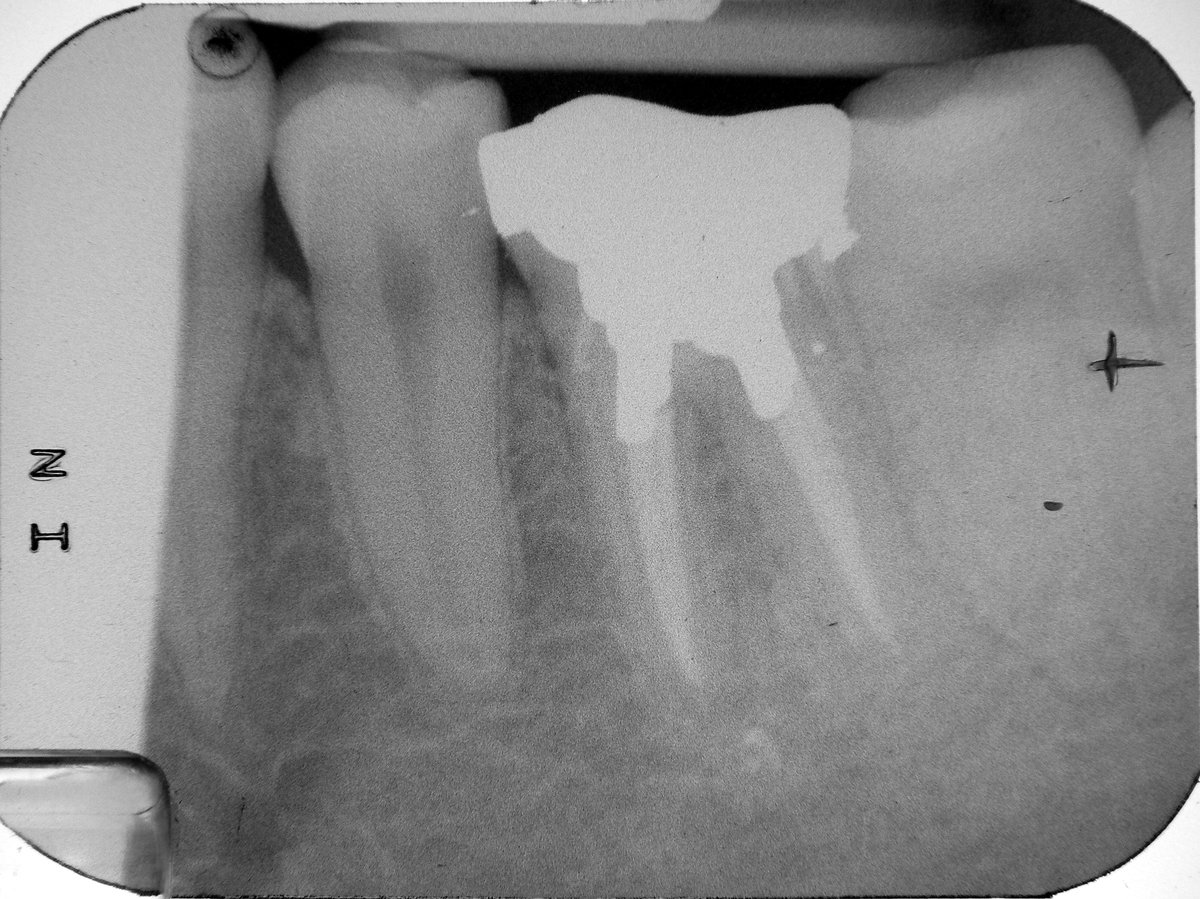

Das Röntgenbild nach Abschluss zeigt die vollständig gefüllten Wurzelkanäle sowie das in die Kanäle eingepreßte Amalgam zur Verankerung der Füllung.